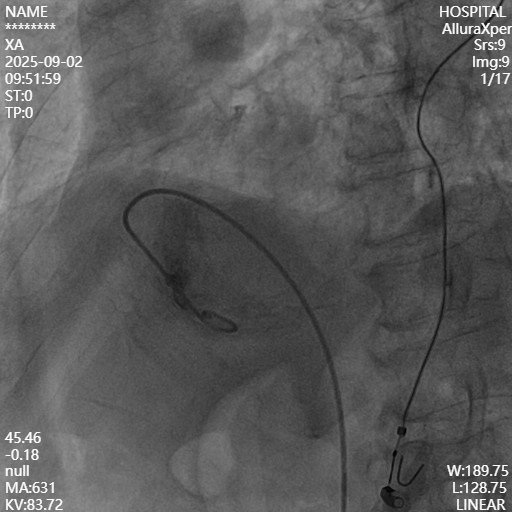

穿刺成功后,使用猪尾导管分别在RAO 30°、LAO 45°造影,RAO 30°右室大小显示清晰,LAO 45°间隔面显示清晰。

接好盐水管路,将起搏器激活后,将调弯制动杆推至一半,施加一定的调弯,在RAO 30°下,将起搏器送入右室,到达目标区域后,分别在RAO 30°、LAO 45°进行造影,RAO 30°下起搏器离心尖位置足够富余,离前后室间沟、三尖瓣距离安全,LAO 45°下,起搏器不够贴向间隔。

建议:RAO下向将起搏器往前送一定距离,略微往心尖方向递进,LAO下,顺时针转动导管,使起搏器更贴向间隔。

确认好到达目标植入区域,后撤保护套筒,轻轻松开导管上所有的制动和调弯,准备进行Mapping。